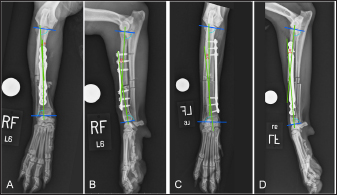

Table 1. Subcategory and procedure times. Comparison of subcategory and total procedure times for cranial and medial plating groups. Data are expressed as mean ± SEM. p-value < 0.05 is considered significant.

Six plated radii in each plating group had some degree of valgus and four plated radii in each plating group had some degree of varus. Frontal plane alignment of cranially plated radii ranged from 11.1° valgus to 3.5° varus. Frontal plane alignment of medially plated radii ranged from 4° valgus to 12.8° varus. Post-procedural frontal alignment (mean ± SEM: 1.8° ± 1.5° valgus and 1.2° ± 1.6° varus in the cranial and medial plating groups, respectively) did not differ between plating groups (p =0.10). Five radii in the cranial plating group had decreased procurvatum and five had increased procurvatum. Seven radii in the medial plating group had decreased procurvatum while three had increased procurvatum (Fig. 5). Sagittal plane alignment of cranially plated radii ranged from 3.0° to 18.2° of procurvatum. Medially plated radii had 5.2° to 21.4° of procurvatum. Post-procedural sagittal plane alignment (mean ± SEM: 11.5° ± 1.8° and 12.0° ± 1.6° in the cranial and medial plating groups, respectively) did not differ between plating groups (p =0.81). Procurvatum was decreased in both plating groups (mean ± SEM: −2.1° ± 1.5° and −1.7° ± 1.3° in the cranial and medial plating groups, respectively) and there was no difference in the magnitude of change in procurvatum between plating groups (p =0.82). Post-procedural radial length ranged from 117.6 to 171.6 mm in cranially plated radii and from 117.9 to 173.8 in medially plated radii. The post-procedural radial length of cranially plated radii was decreased relative to the intact radii (mean difference ± SEM: −1.06 ± 0.71 mm), while the radial length of medially plated radii was increased relative to the intact radii (mean difference ± SEM: 1.11 ± 0.54 mm). The post-procedural radial length was significantly different between plating groups (p =0.004) along with the change in radial length, compared to intact radii, between plating groups (p =0.002). “Near-anatomic” frontal plane alignment was obtained in eight cranial and nine medial-plated radii. “Near-anatomic” sagittal plane alignment was obtained in six cranial and seven medial-plated radii. Post-procedural radii were considered to have “acceptable” frontal plane alignment in one cranially plated radius. Post-procedural sagittal plane alignment was considered “acceptable” in four cranial and three medial-plated radii. Frontal plane alignment was considered “unacceptable” in one radius in each plating group.

Fig. 5. Orthogonal radiographic images of plated radii illustrating trends in frontal and sagittal plane angulation following cranial (A–B) and medial (C–D) plating. Proximal and distal joint reference lines were drawn and joint reference angles were transferred from the intact radii to the plated radii to establish proximal and distal anatomic axes to determine frontal and sagittal plane malalignment. In the cranial plated radius (A–B) there is slight (1°) valgus angulation (A) and decreased (by 7.7° to 5.2°) procurvatum (B), following plating. In the medial plated radius (C–D) there is slight (3.9°) varus angulation (C) and decreased (by 4.4° to 6.7°) procurvatum (D), following plating.